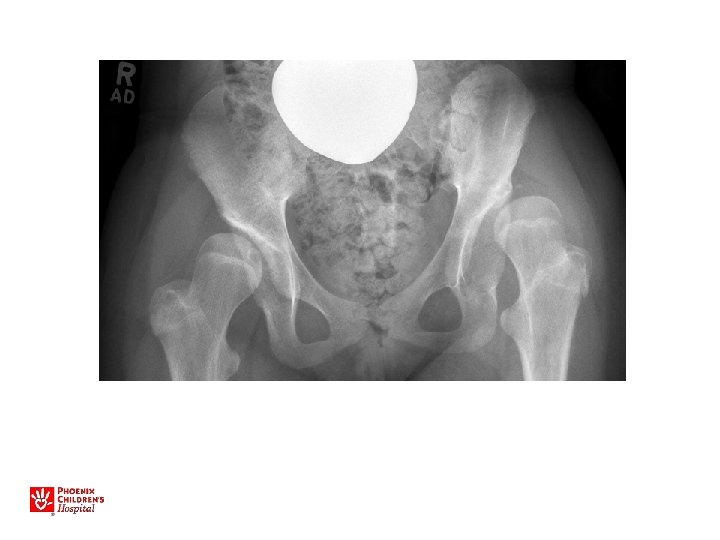

13 yo with hip pain, limp • Family has noted increased pain with activity, not able to walk long distances • No infantile treatment or history • Patient has features of Charcot-Marie. Tooth (associated with hip dysplasia)

• Bilateral periacetabular osteotomies • Bilateral femoral osteotomies